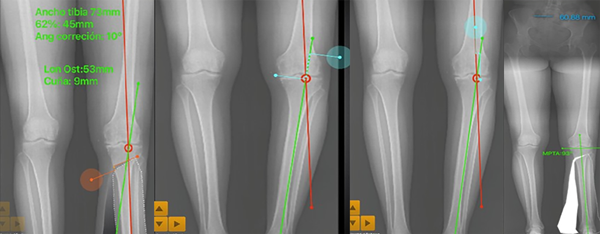

Esta forma de realizar el cambio de tener un objetivo de corrección en grados y convertirlo a milímetros tiene que ver con la manera de aplicarlo al momento de la cirugía: sabiendo las longitudes de un triángulo que se va a formar por la longitud de la osteotomía, y teniendo el valor previamente planificado de apertura en grados, podemos obtener el otro lado del triángulo que corresponde a los milímetros de apertura o de resección para obtener el MAD en el punto deseado de acuerdo a la corrección (figs. 13 a 16).

Figura 13: Cálculo de la longitud total desde la cortical medial a lateral: en este caso es 63 mm, se restan 10 mm para la bisagra lateral y la protección de esta con el pin, teniendo una longitud de osteotomía de 53 mm, con un ángulo de corrección de 9°. Se realiza la fórmula trigonométrica para la cuña de apertura, que es igual a tangente de 9° (0.15) por la longitud de osteotomía (53 mm), dando como resultado: 8.3 mm de apertura.

Figura 14: Proyección de la corrección: se realiza la corrección para tener un MAD que pasa por el 50% de la línea orientación articular de la rodilla, midiendo en MPTA resultante para tener la seguridad que no va a alterar la línea orientación articular (MPTA: 92° - dentro de límite aceptable).

Imagen 15: Cálculo de apertura de la osteotomía en paciente artrósico: la corrección está dirigida al 62%, por lo cual el ángulo de corrección es de 12°. Se considera una DLO, en el caso del fémur distal se realiza un planeamiento de una osteotomía de cierre lateral con una longitud total desde la cortical lateral supracondílea hasta la cortical medial de 60 mm, restando los 10 mm de la protección de la bisagra y espacio para el pin, da una longitud real de la osteotomía de 50 mm (línea roja en el fémur distal), con la fórmula trigonométrica dejando para corregir 4° en fémur y 8° en tibia, dan como resultado 4 mm de cierre en la osteotomía del fémur y en la tibia una longitud total de 63 mm y longitud de la osteotomía de 53 mm, con los 8° restantes de corrección dan 7 mm de apertura, lo que otorga como resultado un MAD que pasa por el 62% planeado.

Figura 16: Medición del mLDFA y MPTA postcorrección: después del planeamiento de la osteotomía se calcula el mLDFA, en este caso es de 88° (valor normal 85-90°) y el MPTA es de 89° (valor normal 85-90°), considerados ángulos corregidos normales y sin alteración de la línea articular.